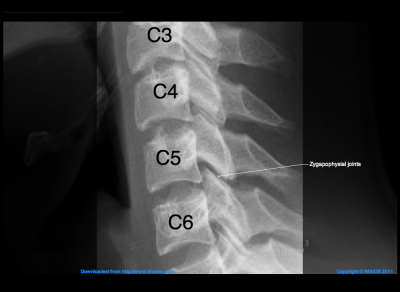

The spine is designed to bend and turn. Along with the intervertebral discs, facet joints (also referred to as Z joints or zygapophyseal joints) enable the spine to bend and twist. Each vertebra has two sets of facet joints. One set of facet joints is located at the top and a corresponding set is at the bottom. Facets joint are small joints a little larger than the size of your thumbnails located in pairs on the back of your spine. They provide stability and guide motion in your back. If the joints become painful they may cause pain in your neck, shoulder, low back, abdomen, buttocks, groin or legs. The pattern and location of pain helps to determine the likely facet joints involved. Working like a hinge, the articulating surfaces of each facet joint are coated with smooth cartilage allowing friction free movement. Although the facet joint bones fit snugly together, there is a lubrication system. The lubricating ‘oil’ is called synovial fluid and resembles uncooked egg whites. This fluid also nourishes the cartilage tissues. A block that is performed to confirm that a facet joint is the source of pain and decrease pain and inflammation in a facet joint or joints.

II. The Facet Joints

• The Facet Joints are the joints of the spine (cervical, thoracic, and lumbar). They contain joint fluid and are lined by cartilage. There are two facet joints at each level of the spine, one on the right and one on the left.

• The function of the facet joints of the spine is to allow movement (flexion, extension, bending side-to-side) and rotation.